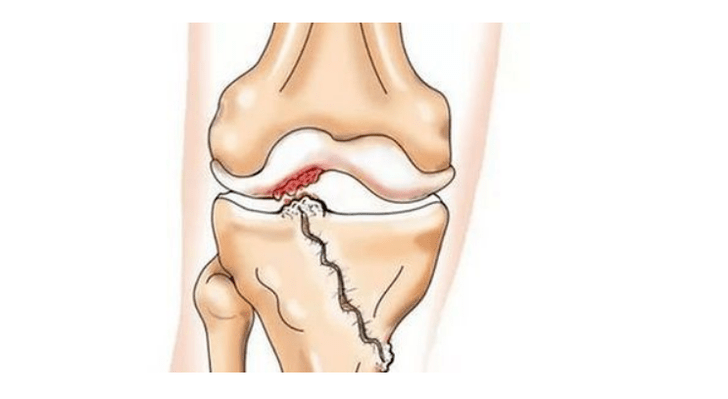

- injuries (fractures, ruptures of the meniscal and anterior cruciate ligament).Unfortunately, in anyone, regardless of age, these injuries cause excessive stress on the cartilage.A fracture of any part of the bones covered with cartilage is accompanied by the formation of an irregularity - a “step”.In this area, when moving, abrasion occurs and osteoarthritis forms;

With osteoarthritis (osteoarthritis), in addition to the gradual destruction of cartilage, loss of its elasticity and cushioning properties, bones are gradually involved in the process.Under load, sharp edges (exostoses) appear, which are incorrectly considered "salt deposits" - with classic osteoarthritis, no salt deposits occur.As osteoarthritis progresses, it continues to “eat” the cartilage.Then the bone deforms, cysts form on it, all structures of the joint are affected and the leg bends.

Lack of cartilage in most affected areas, severe sclerosis (hardening) of the bone, numerous osteophytes, and pronounced narrowing or absence of the joint space.The pain is almost constant, gait is impaired.Mobility is severely limited and joint deformation is noticeable.NSAIDs, physiotherapy and other standard methods of treating osteoarthritis of the knee are ineffective.